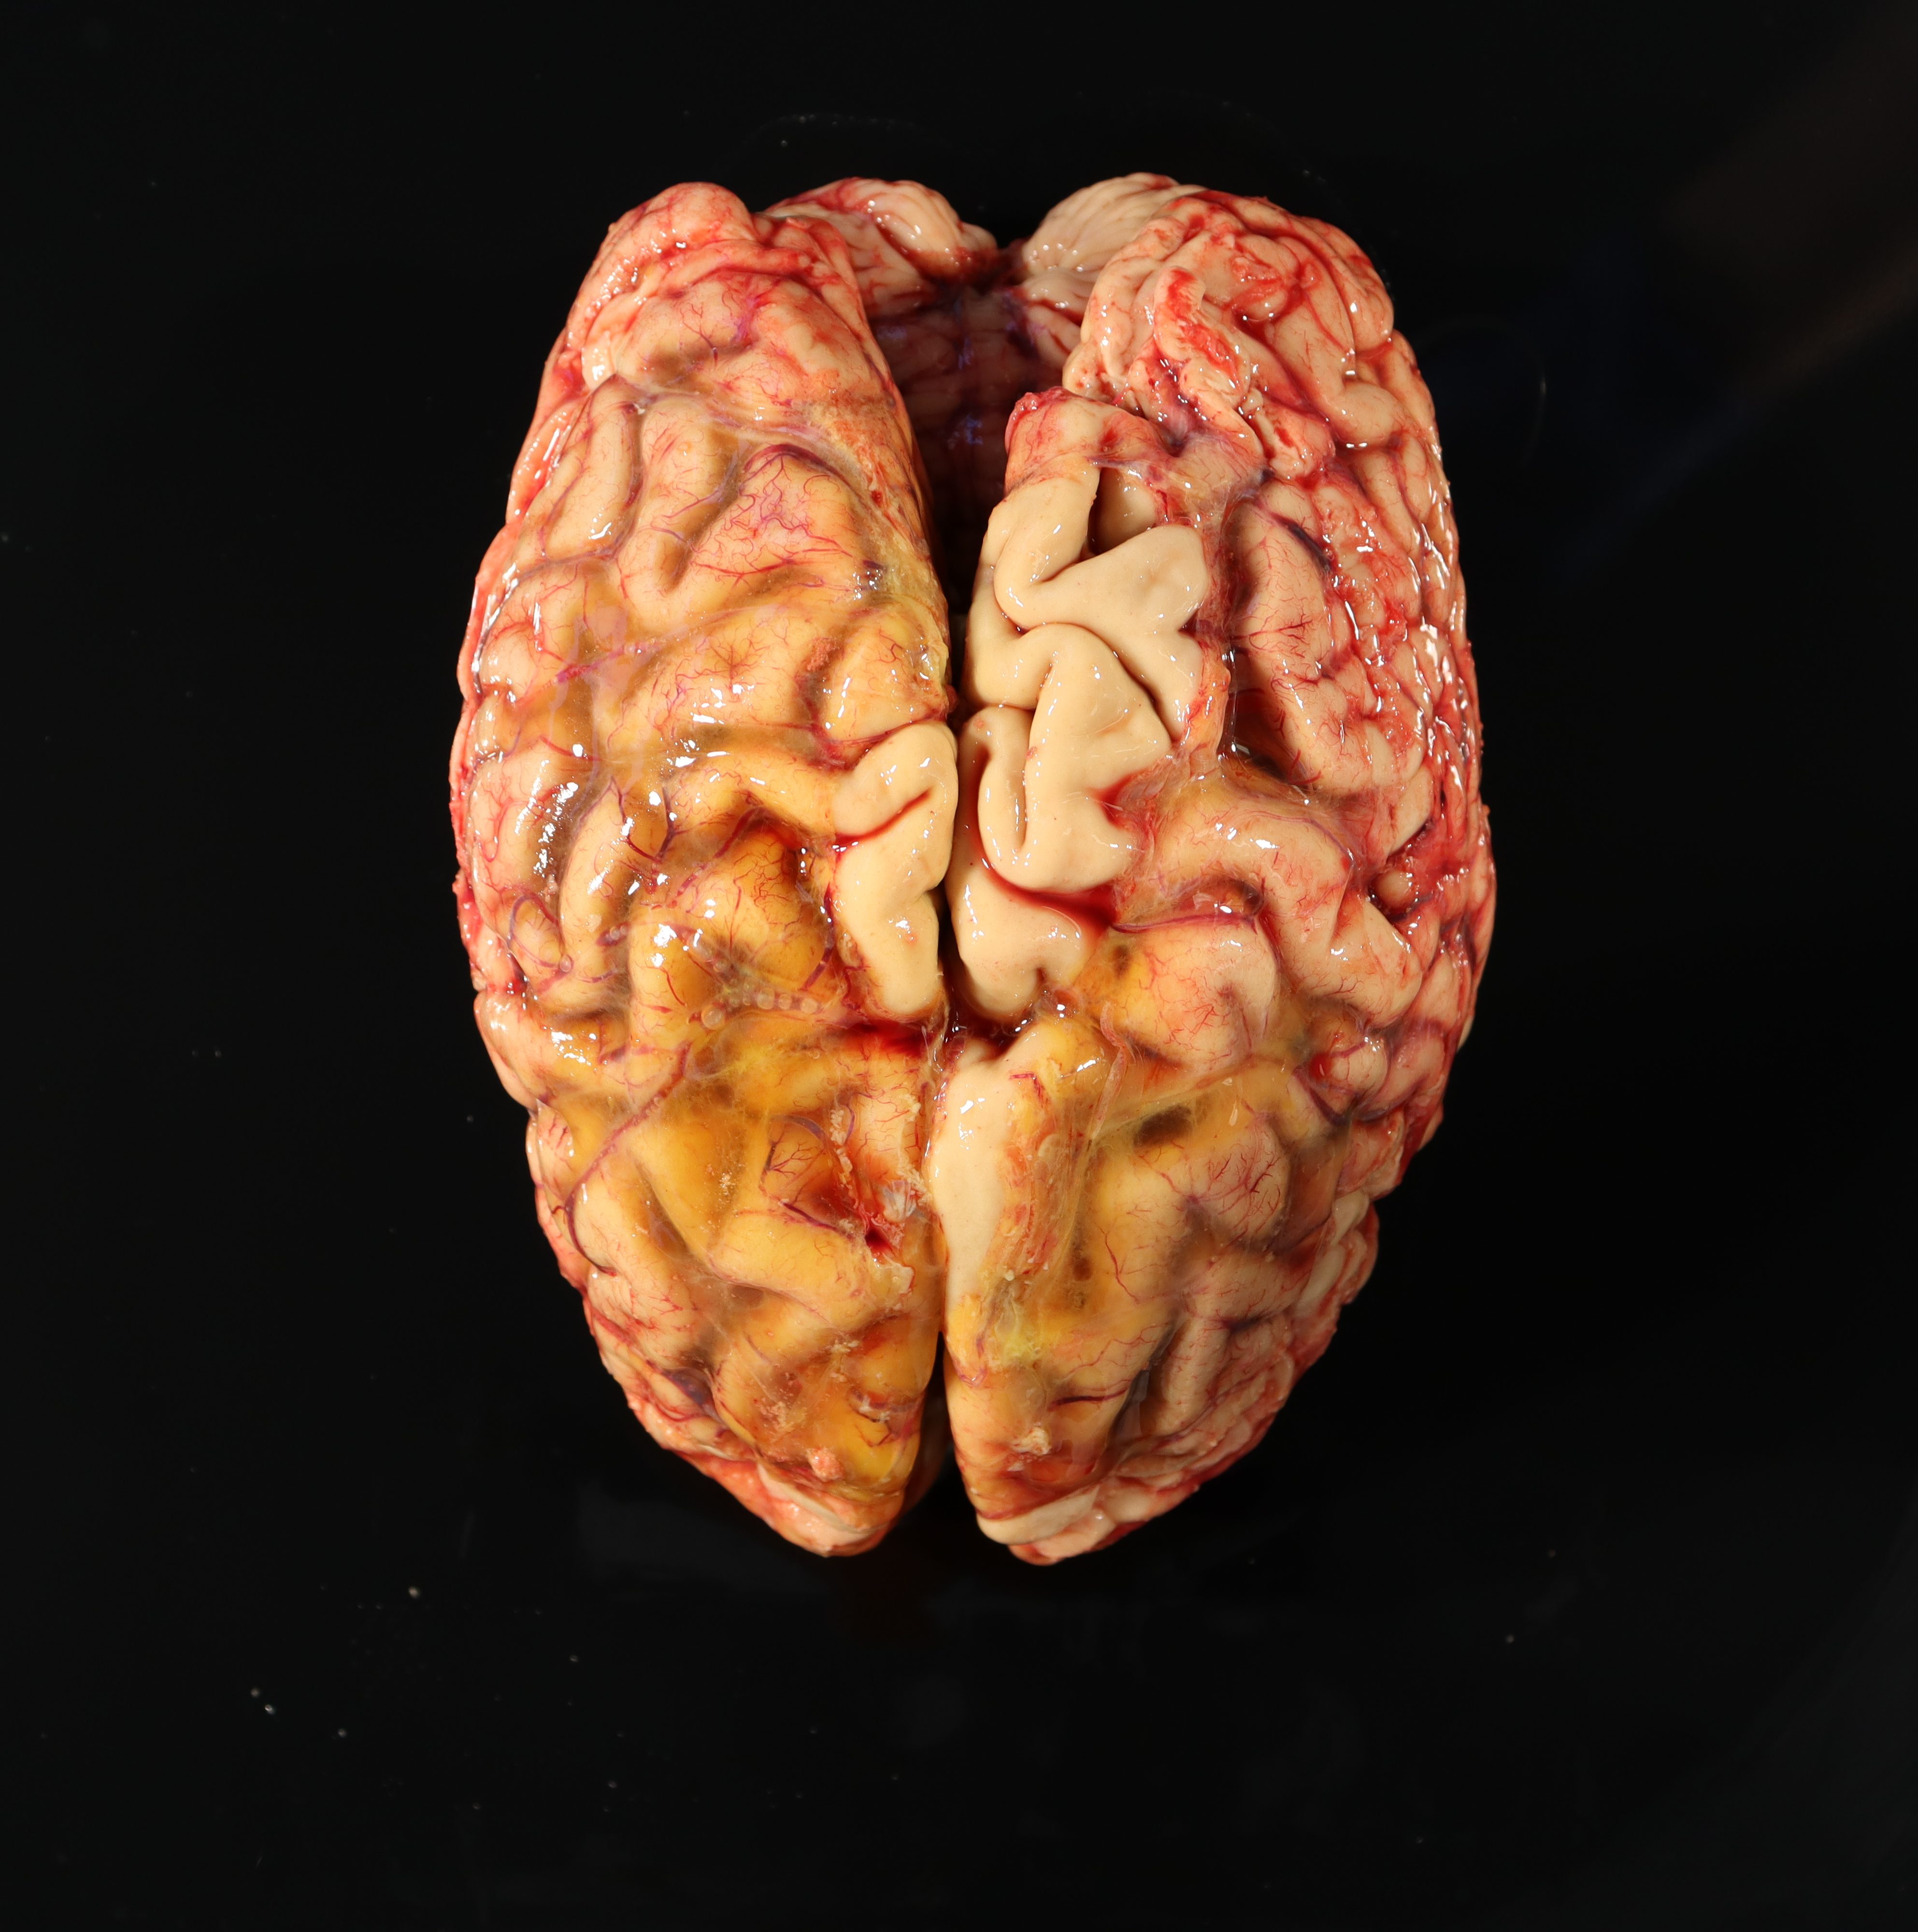

- Examine the external surface of the brain for any asymmetries, areas of softened texture, or discoloration. Identify and note the condition of cranial nerves when possible. Note if the cerebral vessels are congested or if there is atherosclerosis in the circle of Willis.

- Note if there is any evidence of atrophy, with increased space within sulci between gyri (atrophy can also correlate with lower brain weight for size of the individual).

- Determine if any herniation is present by checking the following areas for a discrete depression or “shelf” and then measuring the depth of any impressions seen on the affected and unaffected sides. For additional information see the Herniations Article.

Subfalcine herniation – examine the surface of the central fissure for any depressions caused by tissue pushed up against and under the falx in the midline – hernations in his location are measured on the medial-lateral axis. The hemispheres can be gently separated to view any tissue obstructing the view of the corpus callosum. Alternatively, this can be visualized in cross section.